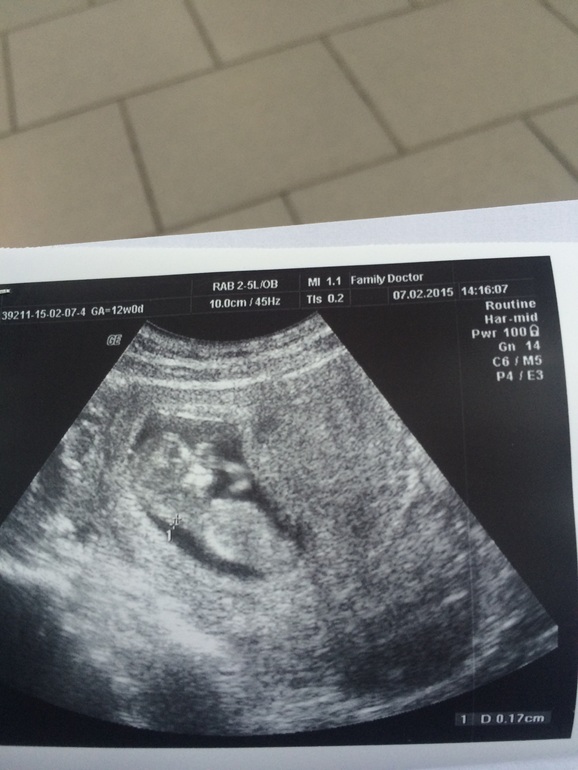

2-ая беременность 12 недель.

В субботу были на плановом УЗИ , срок 12 недель , малыш весит 50 грамм

Узист сказала что развивается наше чудо согласно срокам, пдр поставили на 20.08.15, а через месяц возможно узнаем кто прячется в животике)я счастлива !!